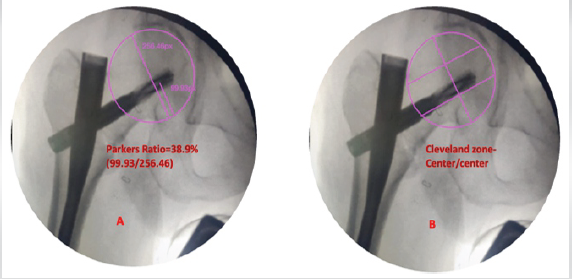

Post-operative radiographs were obtained, and they showed a neutral reduction, a Baumgaertner’s Tip Apex Distance (TAD) of 19.73 mm, the neck shaft angle was 138°, and Parker’s ratio was 38.9% (Figs. 2 and 3).

Figure 3: (a) Parker’s ratio 38.9%, (b) Cleveland zone-center/center

The post-operative fracture gap was <1 mm, and Garden alignment index was good, and the center of the helical blade was placed in the Cleveland zone center–center. The reduction quality was good according to the Baumgaertner reduction quality criteria, and excellent according to the Chang reduction quality criteria, respectively.